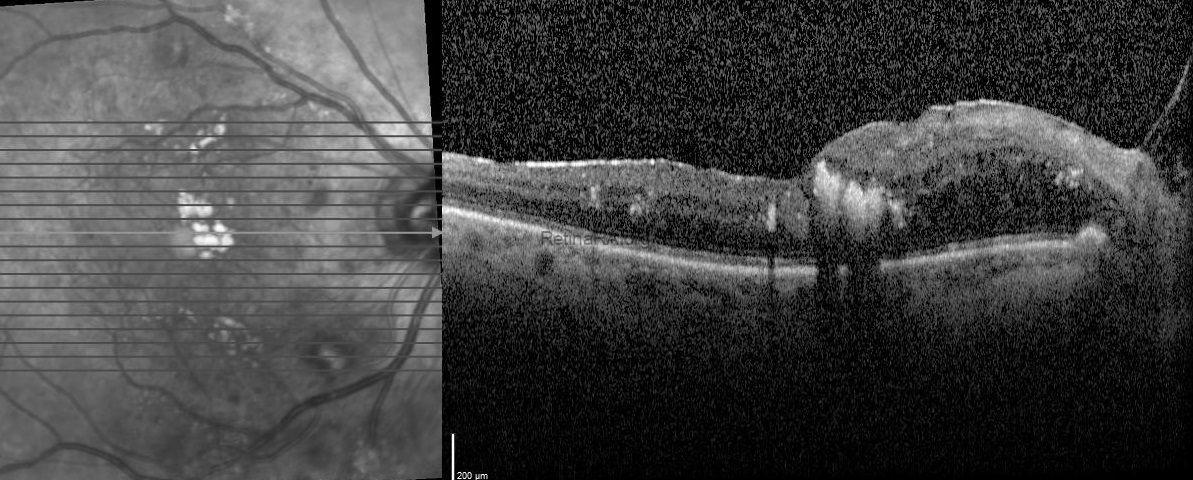

A 65-year-old female diagnosed with type 2 diabetes mellitus and impaired lipid metabolism with hypercholesterolemia presented with moderately graded non-proliferative diabetic retinopathy with widespread hard exudates (HEs) at the macula (Figure 1, top). The HEs appeared as golden-yellow lesions at the fovea and pale yellow-colored HEs surrounding the foveal lesion were also detected in temporal and superior to the fovea (Figure 1, top). Spectral domain optical coherence tomography (SD-OCT) scans through the fovea showed serous macular detachment and nasally cystoid macular edema in addition to an unusual finding of intensely hyper-reflective line deposits over the retina pigment epithelium without posterior shadowing which was termed as Onion Ring Sign. (Figure 1, middle-bottom). Two months after injection of dexamethasone implant (Ozurdex®; Allergan, Inc., Irvine, CA, USA; 700 μg) in addition to systemic lipid lowering therapy, cystoid macular edema and serous retinal detachment disappeared besides the onion ring sign resolved as subfoveal exudate plaque (Figure 2). However, there was not any increment in visual acuity.

Composite fundus photo and OCT scans of the patient with type 2 diabetes mellitus and hypercholesterolemia.